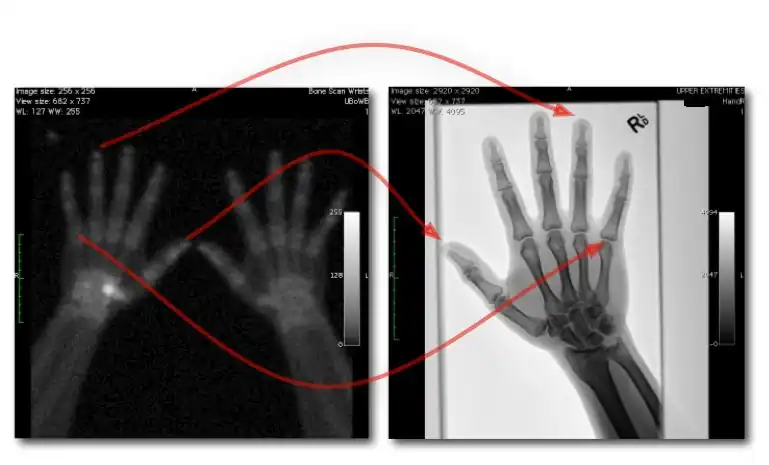

Digital image receptors have been increasingly applied in general radiography since the turn of the century. Early studies indicated its superior image quality relative to film/screen technology in skeletal radiography[1][2]. On this basis, refinements of exposure technique have also occurred[3][4][5][6]. Furthermore, dose comparisons with traditional radiography and various forms of Computed Radiography (CR) with direct and indirect Digital Radiography (DR) have been made[7][8][9]. In addition, the performance of digital image receptors for fluoroscopic applications has also been investigated[10].